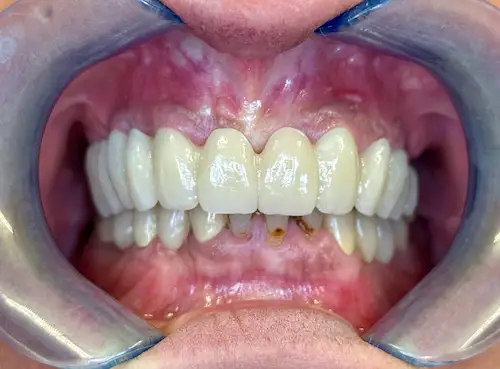

All-on-4 ® – Patientenfall

Bei Zahnlosigkeit oder nicht mehr erhaltungswürdigen Zähnen wünschen sich die Patient*innen der Praxisklinik Herne natürlich zeitnahe und minimalinvasive Lösungen. Dank des All-on-4 ® / All-on-6 ®–Konzepte können wir ihnen diesen Wunsch oftmals innerhalb nur eines einzigen Behandlungstages erfüllen: 4 bzw. 6 Zahnimplantate werden gesetzt und bilden im Folgenden die Grundlage für den passenden festsitzenden oder herausnehmbaren Zahnersatz. Die einzelnen Behandlungsschritte veranschaulichen wir Ihnen anhand eines aktuellen Patientenfalls aus diesem Jahr.

Der Tag der Operation ist gekommen: Im ersten Schritt werden die noch vorhandenen Zähne gezogen sowie die Wurzeln und vereinzelte Zysten restlos entfernt. Dies erwies sich im vorliegenden Fall als extrem komplex und folgenreich: Beim Extrahieren gingen Teile der Knochenwände verloren, was einen deutlichen Mehraufwand beim Aufbau des Kieferkamms nach sich zog. Zuzüglich zu Knochenersatzmaterial verwendete Dr. Mintert dafür 2 Collagen Blöcke, 2 Membranen und 0,3 ml Emdogain. Letzteres dient der Entwicklung von zahnstützendem Gewebe. Auch Eigenknochen aus einem zweiten OP-Gebiet kam zum Einsatz. Im Oberkiefer wurde außerdem ein sogenannter Sinuslift durchgeführt, der – vereinfacht gesprochen – die Kieferhöhlen anheben soll. Nun waren die Grundlagen für den nächsten Schritt geschaffen: Eine eigens angefertigte Bohrschablone ermöglicht die navigierte Implantation. So fanden alle acht Implantate trotz ungeplanter Komplikationen ihren rechten Platz im Mundraum. Abschließend wird L-PRF Plasma, d.h. zentrifugiertes Eigenblut eingebracht, um die Wundheilung zu unterstützen. Als Zahnersatz werden zwei festsitzende Keramikbrücken gewählt und auf künstliche Keramikaufbauten geklebt. Diese wiederum sind mit jeweils vier Implantaten verschraubt.

All-on-Four Zahnersatz nach OP - Patientenansicht